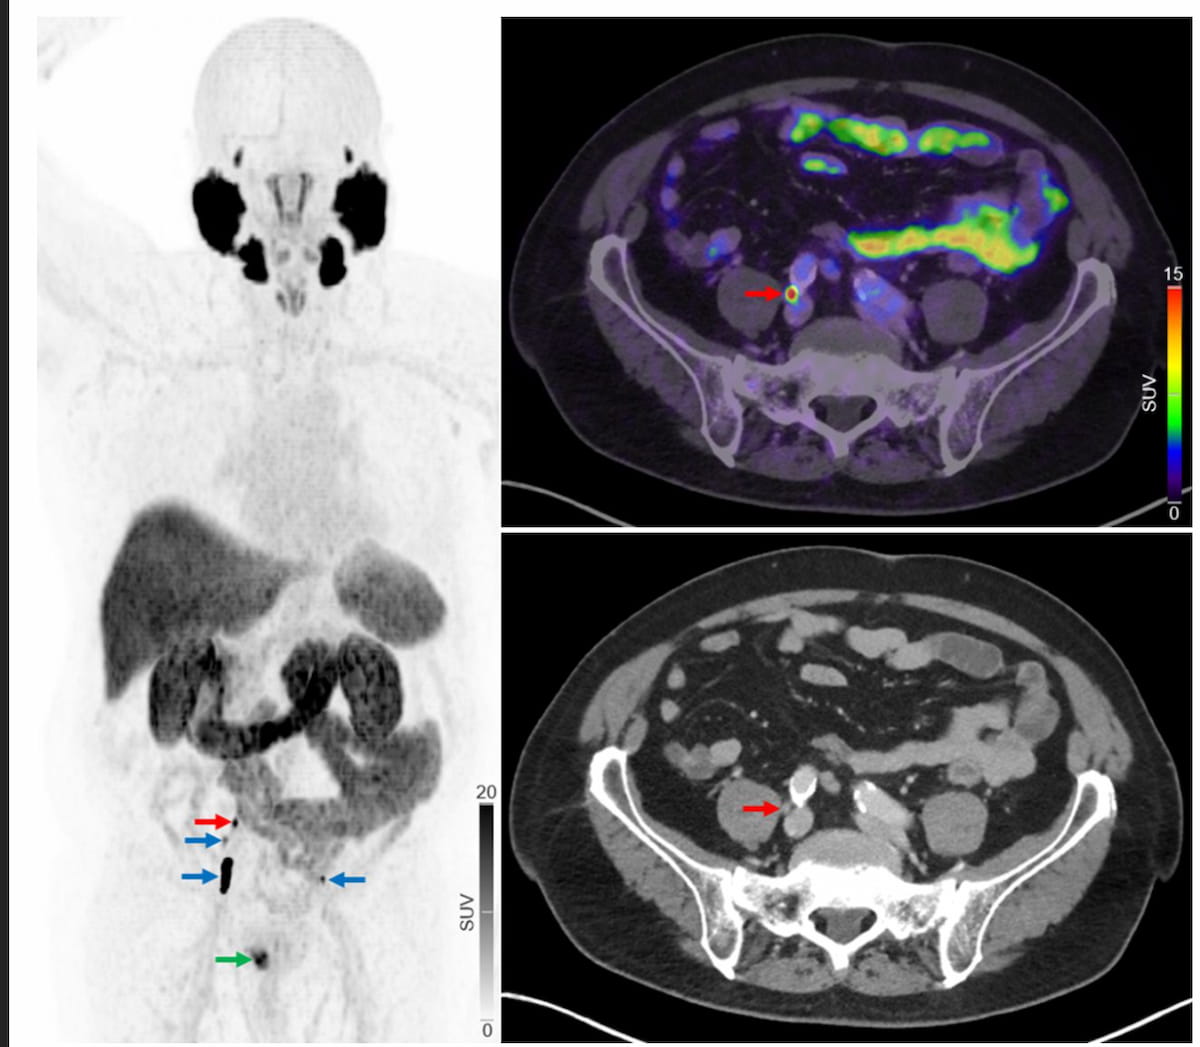

In the 160-patient study comparing 18F-PSMA 1007 PET/CT and 18F-NaF PET/CT, the use of 18F-PSMA PET/CT led to 38 patients being restaged as having more advanced prostate cancer.